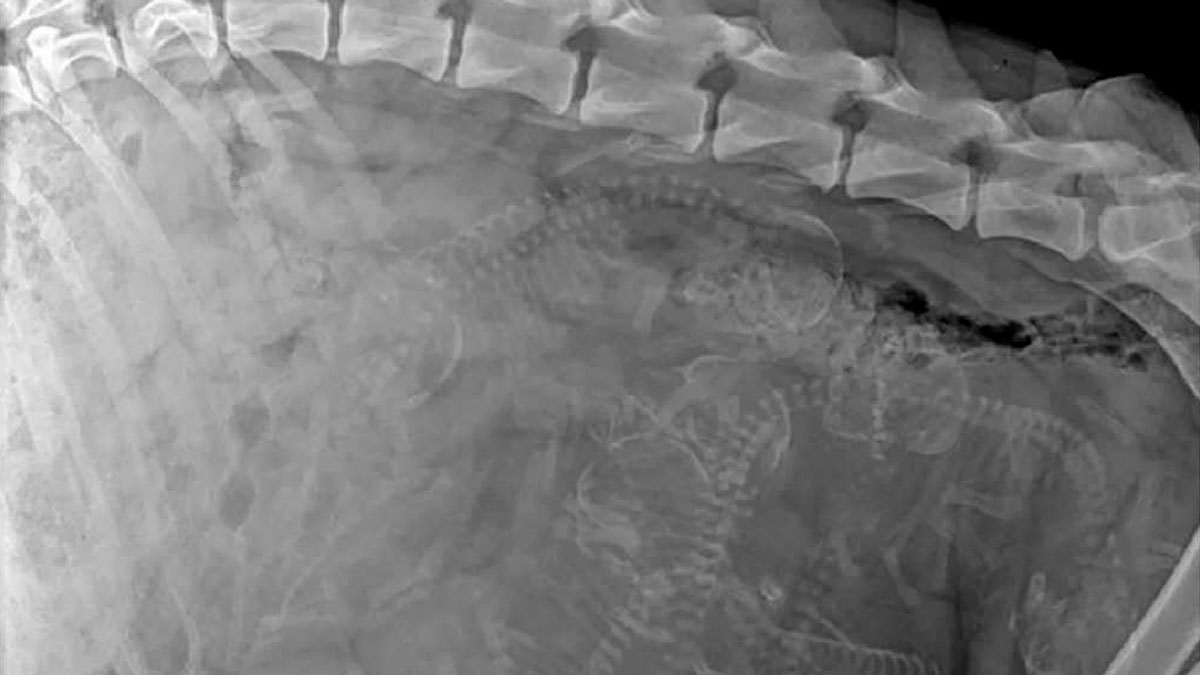

Luckily, the internet offers us exciting knowledge in the form of bite-sized interesting facts. Places like this Instagram page share fun tidbits that you might've not seen before yet. "Let's explore the wonders of the universe together!" is their motto. So, scroll down and see what a dog's belly full of little puppies looks like and what unusual form of payment one city in Romania now accepts for public transport!